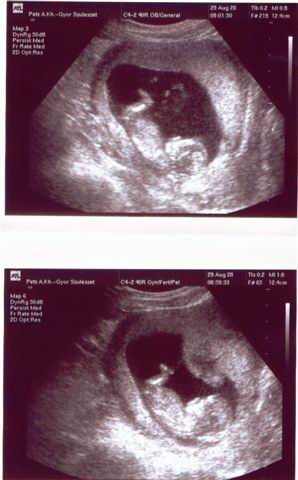

Egyelőre még reménykedünk, mert egy dolog, hogy babát várunk, de szeretnénk biztosak lenni benne, hogy egészséges, rendben van, hiszen 40 felett, első babával minden előfordulhat.